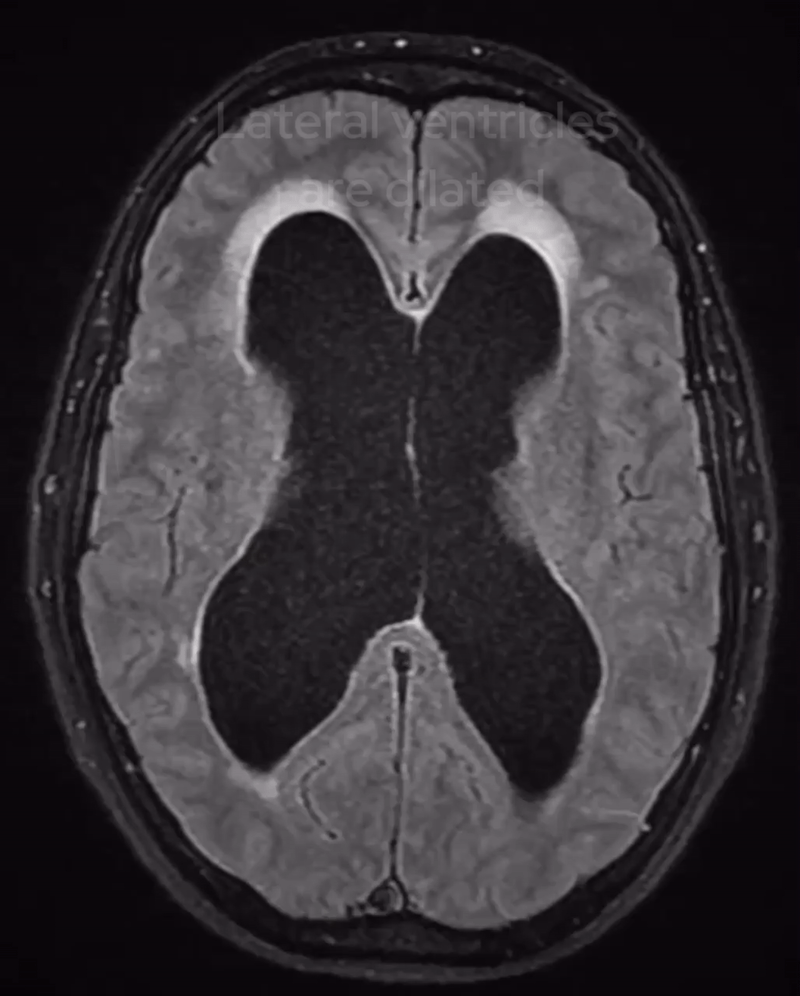

In this case, we immediately notice marked dilation of the lateral ventricles, an important clue. However, when we look further down at the fourth ventricle, it appears normal in size.

This suggests obstructive hydrocephalus, meaning something is blocking the normal flow of cerebrospinal fluid (CSF). What’s causing the obstruction?

The lateral ventricles are dilated but the 4th ventricle is normal in calibre suggesting there is obstructive hydrocephalus.

Going back to the FLAIR sequence, we see high signal surrounding the lateral ventricles—this is transependymal oedema, an important indicator of acute obstructive hydrocephalus.

What’s happening here?

- The blockage at the foramen of Monro disrupts CSF flow.

- Pressure builds up in the lateral ventricles.

- Fluid leaks into the surrounding brain tissue, causing oedema in the periventricular white matter.

This is a serious finding: it suggests acute hydrocephalus, which, if untreated, can lead to brain herniation and death.

Fluid leak in the context of acute hydrocephalus can lead to transependymal oedema and the appearance of hyperintensity on FLAIR images.